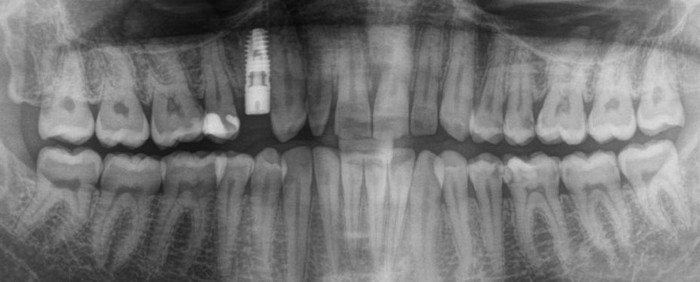

Помимо визуального осмотра

нам требуется провести рентгенологическое исследование. В данном случае простого ОПТГ (Панорамного снимка зубов) нам будет недостаточно. Потребуется КЛКТ (Конусно-лучевая компьютерная томография).

ОПТГ (Ортопантомограмма) — обзорный снимок зубочелюстной системы. Данный снимок является плоскостным, а значит происходит наложение каждой детали снимка послойно друг на друга. Следовательно, рассмотреть объект исследования, в частности место планируемой имплантации, во всех плоскостях, под иным углом или другой проекции невозможно.

КЛКТ (Конусно-лучевая компьютерная томография) — 3D объемный снимок, напротив дает нам такую возможность.

В данном случае, объёмов костной ткани достаточно для стабилизации оптимального по размеру имплантата, а качество десны делает возможным формирование эстетического контура без дополнительных процедур:

И контрольным снимком